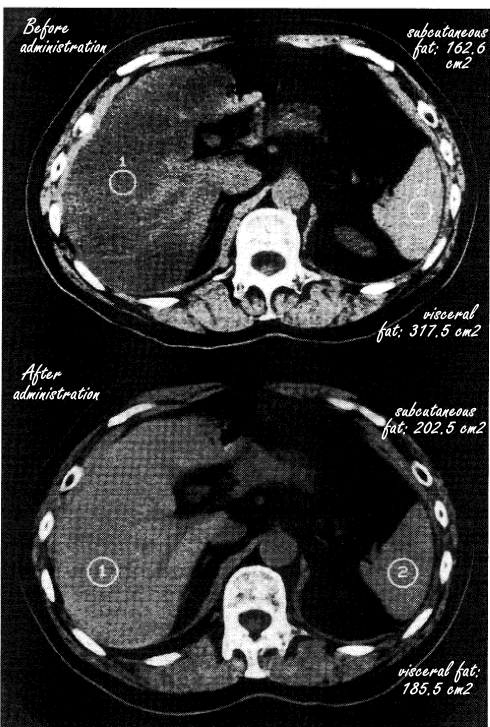

Tijdens de suppletieperiode verminderde volgens scans de hoeveelheid vet in de lever, en nam bovendien de hoeveelheid buikvet significant af. Op de scans onder de tabel zie je scans van een kennelijk representatieve proefpersoon.

De conclusie van de Japanners ligt voor de hand. "Pantethine improved fatty liver with hypertriglyceridemia and reduced visceral fat", schrijven ze.

Tegenover de afname van het buikvet staat misschien een toename van het onderhuidse vet. (Yep, dat laatstgenoemde effect was niet statistisch significant, maar dat was bij een onderzoek met meer proefpersonen wellicht anders geweest.) Het zou verrektes interessant zijn om eens te kijken naar het effect van pantethine-suppletie bij mensen die, als gevolg van een afslankdieet of een bewegingsprogramma, minder kilocalorieën binnenkrijgen dan ze verbranden.